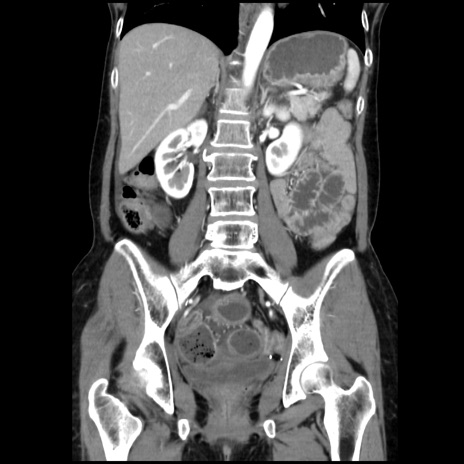

症例32(冠状断像)

【症例】40歳代 女性

【主訴】上腹部痛、嘔気・嘔吐

【現病歴】約9時間前頃から急に上腹部痛、嘔気、嘔吐が出現。改善しないため救急要請。

【既往歴】子宮頚癌(広汎子宮全摘術、放射線療法)、腸閉塞

【身体所見】腹部:平坦、軟、腸雑音亢進、上腹部を中心に腹部全体に圧痛あり。

【データ】WBC 8400、CRP 0.03